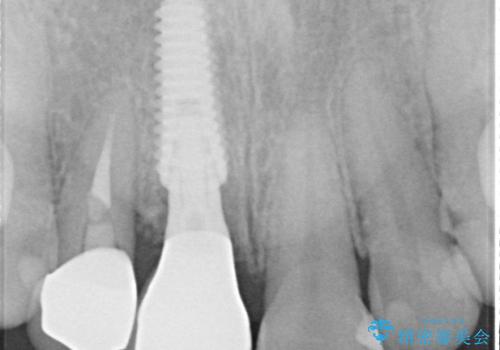

- 前歯のセラミッククランが外れてしまったとのことで来院された患者様です。

診察をしたところ、歯根に縦破折が認められ、抜歯が必要と判断されました。

抜歯、インプラント埋入、仮歯の装着が同時に可能な1DAYインプラントが適用可能と判断されたため、インプラントによる補綴治療を行うこととしました。